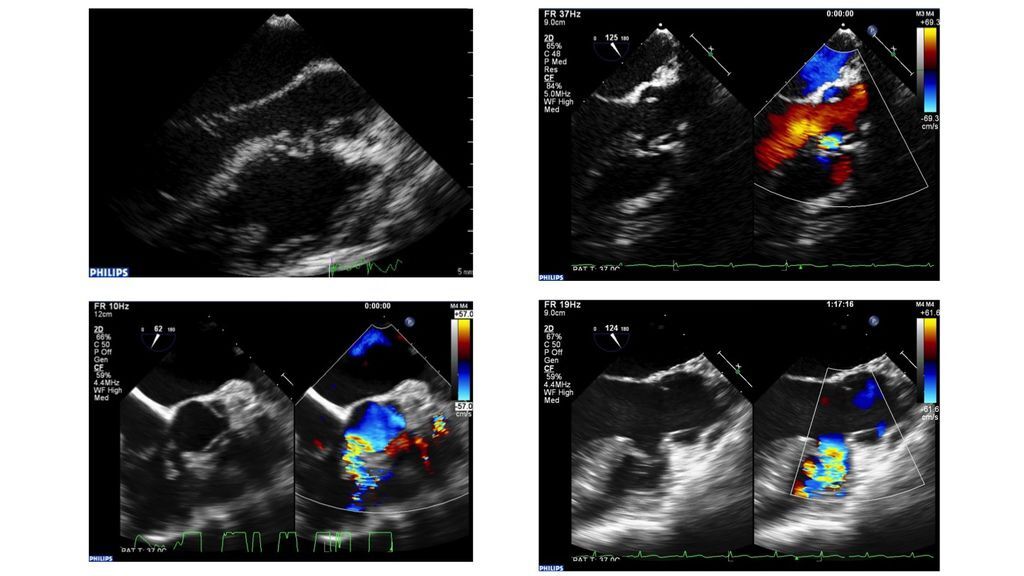

進行第二階段前,針對大部分的個案,為了讓治療當下有好的影像監控,我們常規會進行經食道超音波的檢查。因為經食道超音波檢查在清醒時做不太舒服(就像做胃鏡一樣),因此團隊中會有麻醉科醫師幫病患進行全身麻醉。進行全身麻醉雖然聽起來有點麻煩,但其實對病人安全與治療成效而言實際上是多了一層保障(以我在波士頓兒童醫院進修時的經驗,他們幾乎對每一個接受侵入性治療的患者都進行全身麻醉,由此可見其重要性)。

那怎麼知道關閉器是不是放在理想的位置呢? 這時候除了要在左心室再打一次顯影劑看看缺損與關閉器的位置外,就要靠經食道超音波的幫助,更仔細評估每一個角落、看關閉器是否將缺損堵住、是否影響到主動脈與三間瓣的功能。當然,過程中一直要監看心電圖,注意是否有傳導障礙的發生。如果位置不理想,別擔心,關閉器可以再收回載送系統內,重放一次就好了!